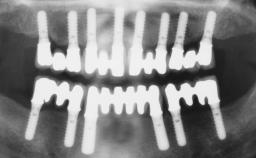

Immediate Loading of Six Implants in the Mandible and Six Implants in the Maxilla and Final Restoration with Full-Arch CAD/CAM Metal Framework FDPs Involving Digital Planning and Guided Surgery

# of Implants 12

Modality 6+ implants with immediate loading